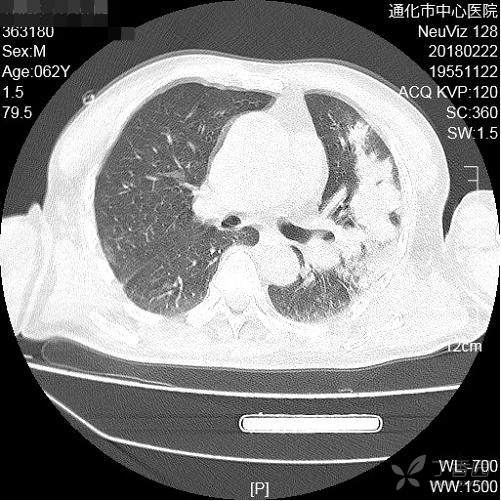

男,62岁。一氧化碳中毒昏迷而冻伤,因发现急性肾功能衰竭入住肾内科,入院后发现寒战发热、咳嗽、咯粘稠黄痰。嗜酒:2两/日,吸烟:3-5支/日。无糖尿病。

血常规白细胞1.2万。

治疗:头孢哌酮舒巴坦静点

考虑什么细菌感染?